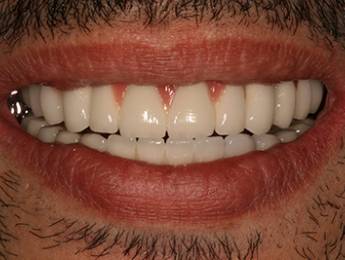

Nagymértékű fogkopás, erózió, csikorgatás a teljes rágóapparátust túlterhelve okoz reménytelennek tűnő helyzeteket.

Ebben az esetben implantátumok , koronák és hidak segítségével változtattunk a páciens fogainak érintkezésén. 6 hónapig ideiglenes hidakkal teszteltük a megváltoztatott harapási pozíciót. Ezután készültek el a végleges fix pótlások.